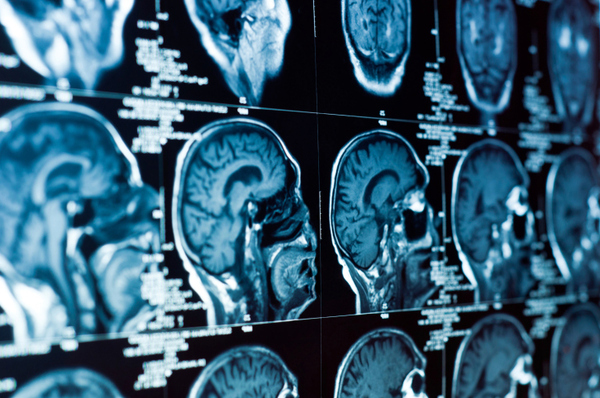

Using powerful microscopes and imaging devices, Rice University researcher Amina Qutub can observe brain cells in a glass container and the connections they make with each other.

Normal brain activity results from those cells — called neurons — linking together in complex networks, and researchers are seeking a better understanding of how that happens.

In the laboratory there is a piece of abstract art that is composed of images of neuron networks, showing their vast complexity.

"They form very elaborate and beautiful structures," Qutub said of the neurons, "and the different network structures relate to what they do, their function. What we are trying to figure out is what are the chemical signals that lead to a particular structure and, in turn, how does that chemical structure lead to the electrical signals that you get when you have active neurons."